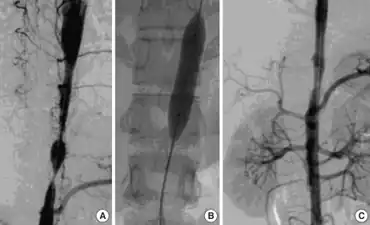

a) 3D-CT angiography- focal stenosis b) percutaneous transluminal angioplasty using balloon catheter c) stent in aorta

Most people with Takayasu’s arteritis respond to steroids such as prednisone. The usual starting dose is approximately 1 milligram per kilogram of body weight per day (for most people, this is approximately 60 milligrams a day). Because of the significant side effects of long-term high-dose prednisone use, the starting dose is tapered over several weeks to a dose which controls symptoms while limiting the side effects of steroids.

Patients who do not respond to steroids may require revascularization, either via vascular bypass or angioplasty and stenting. Outcomes following revascularization vary depending on the severity of the underlying disease. [15]